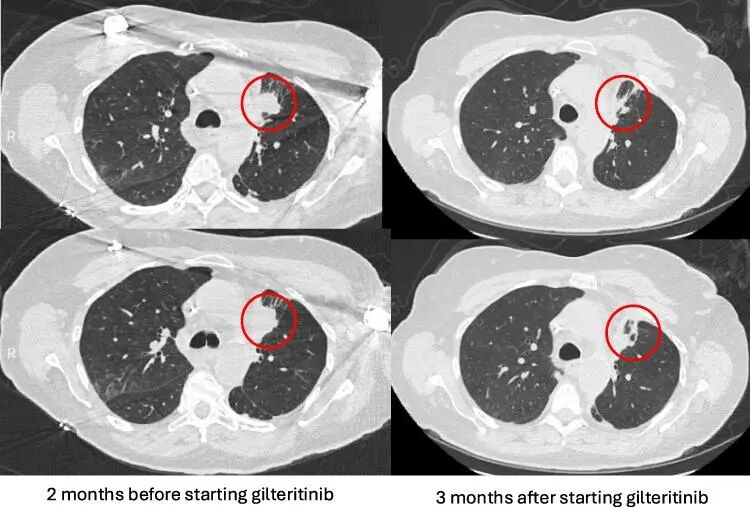

该患者开始使用吉瑞替尼(80mg/天),3个月后,影像学检查显示左上肺叶肿块缩小,且未出现明显副作用。随后增加剂量(120 mg/天)进行维持治疗,约16个月后的复查提示:部分获得性耐药相关信号在基因分型中出现“持续被清除”的趋势。

左上肺叶肿块缩小

更重要的是——截至文章发表时,患者仍在使用吉瑞替尼,并通过远程医疗追踪持续保持良好状态,CT检查显示原发肿瘤稳定,癌胚抗原(CEA)水平保持较低。且没有出现包括骨髓抑制在内的影响到患者继续治疗的副作用。